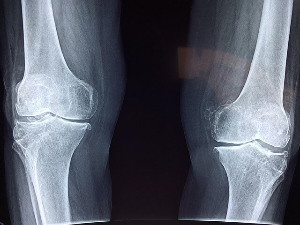

출산 후 관절통은 손목, 무릎, 허리, 발목 등 다양한 부위에서 나타날 수 있습니다. 아기를 안을 때 손목을 과도하게 사용하면 손목터널증후군(수근관 증후군)이 발생할 수 있습니다. 무릎에 통증을 느끼게 되며 이 것은 연골 손상이나 관절염 초기 증상일 수 있습니다. 출산 후 갑자기 체중이 감소하면서 무릎 연골이 약해지고 통증이 발생할 수 있습니다. 계단을 오르내릴 때 무릎이 뚝뚝 소리가 나거나 시큰거리는 느낌이 들 수 있습니다. 허리에 요추염좌 또는 골반 불균형이 생길 수 있습니다. 임신과 출산 과정에서 골반이 벌어지고 허리에 부담이 증가합니다. 출산 후 바르지 않은 자세로 수유하거나, 오랜 시간 앉아 있으면 허리 통증이 심해질 수 있습니다. 발목 및 발바닥에 족저근막염과 발목염좌가 생기는 경우도 있습니다. 체중 변화와 함께 발바닥과 발목에 부담이 증가하면서 통증이 발생할 수 있습니다. 출산 후 갑자기 운동을 시작하면 족저근막염(발바닥 통증)이 심해질 수 있습니다. 출산 후 관절통이 3개월 이상 지속되거나, 일상생활이 어려울 정도로 심하면 병원 검진이 필요합니다.